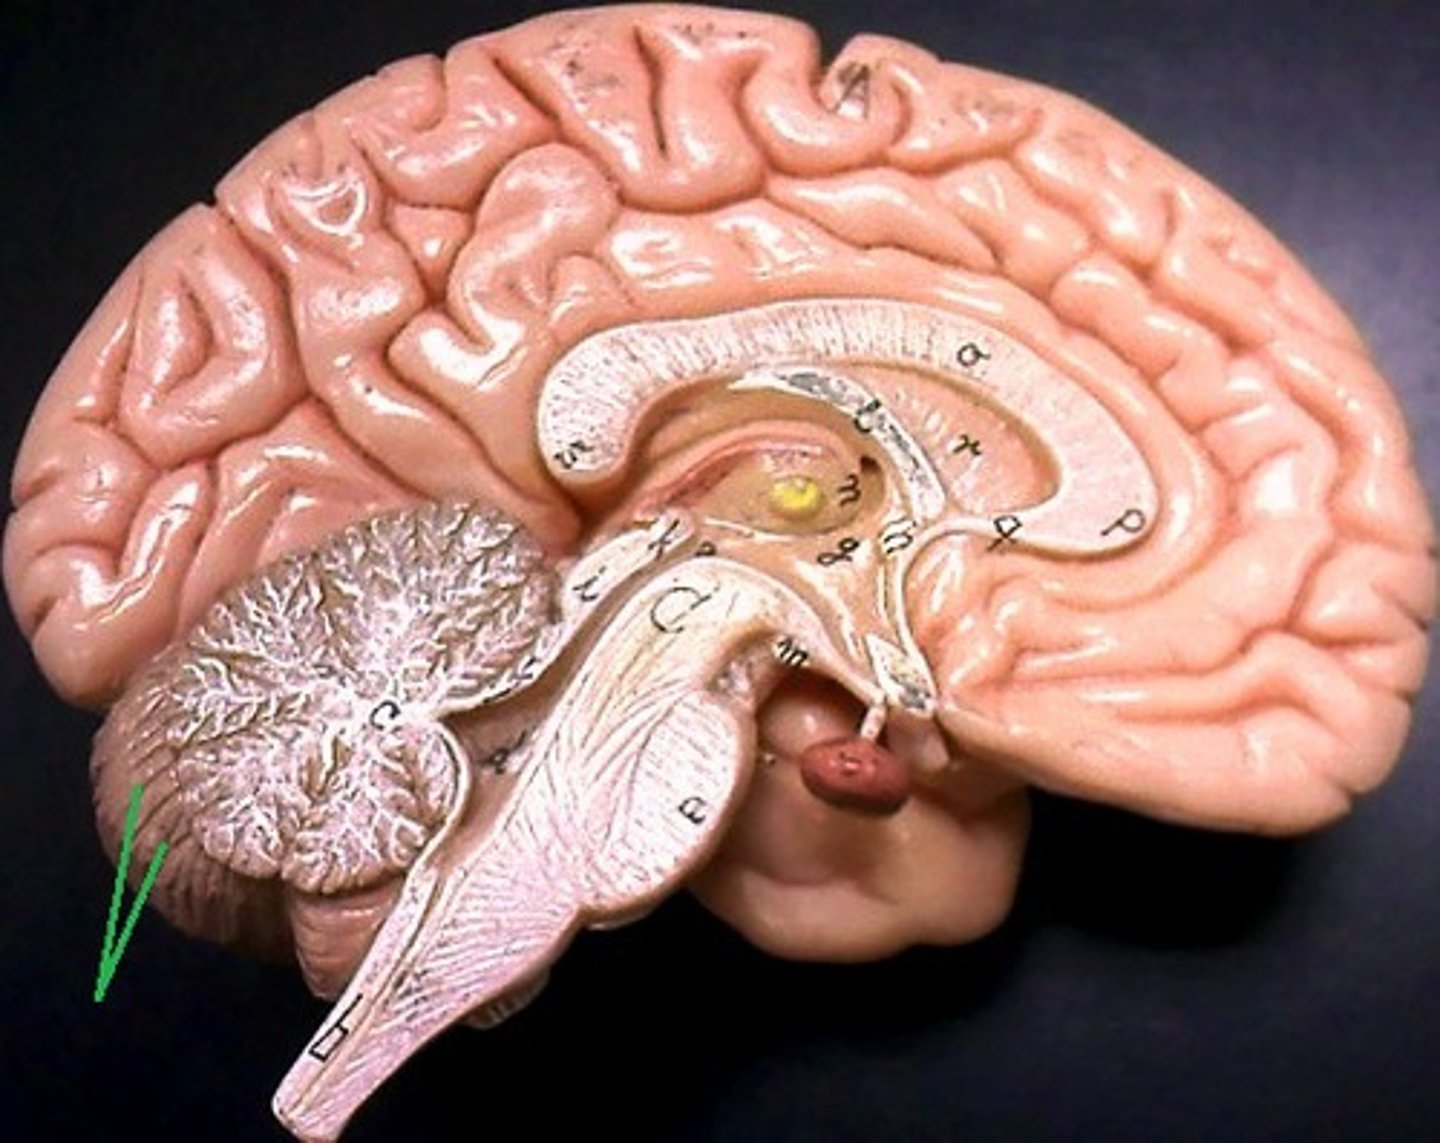

Cerebellum

anterior lobe of cerebellum

posterior lobe of cerebellum

cerebellar peduncles

arbor vitae